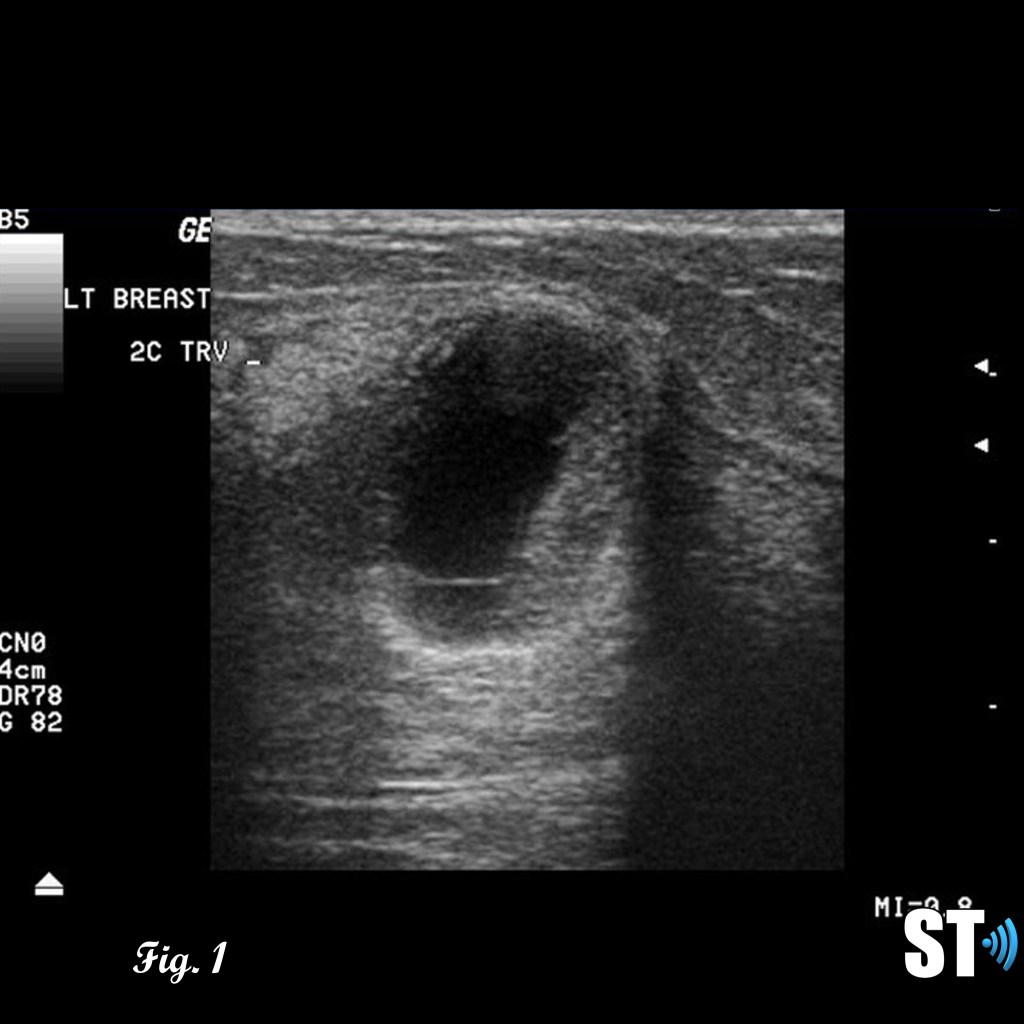

Ultrasound

Patients with suspicious or palpable masses are often referred to ultrasound for further evaluation. Phyllodes tumors can exhibit characteristics similar to fibroadenomas such as; hypoechoic, well demarcated, solid. Features like rapid growth, large size at presentation and cystic areas can raise suspicion for phyllodes.

Fig. 1-3 17 yo Female with complex cystic/solid breast lesion that resulted to be phyllodes.